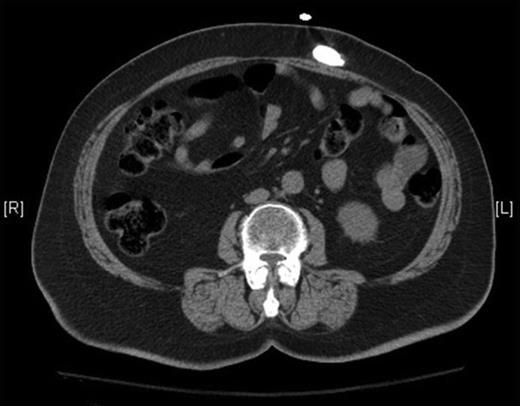

Two months later, the patient returned with complaints of headache and visual loss. CT scan of the head showed tumor recurrence in left parietal region, with recurrence of the subgaleal fluid collection, and shunt series showed the distal shunt catheter tightly coiled within the abdomen and overlying the left mid-abdomen (Fig. 1B and 2). The patient was afebrile, the abdomen was soft and non-tender with normal peristalsis and no signs of peritoneal irritation. Because of concern for hydrocephalus, the patient was taken back for distal shunt revision. However, due to the extent of tumor re-growth, the patient was not a candidate for tumor resection. Intra-operatively, the distal shunt catheter was found to have migrated superficial to the rectus sheath, where it had become encapsulated in a pre-peritoneal CSF pseudocyst. The distal portion of the tubing was cut off and new distal tubing was attached with a straight connector. The straight connector was subsequently stitched to the cyst wall to prevent future retraction. Abdominal X-ray reconfirmed peritoneal placement of the distal shunt tip (Fig. 1C).

Pre-operative CT radiograph without contrast of the abdomen confirms extra-peritoneal migration of the distal shunt tip.